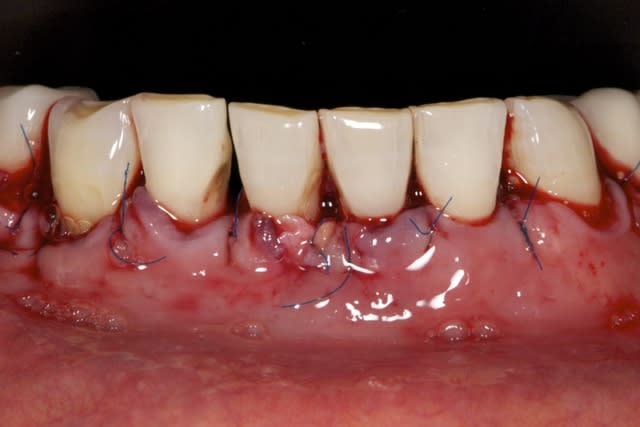

Je stressais pas mal sur ce cas quant à la réussite du conj. enf. avec lamb. tracté coronairement. Mais le résultat est acceptable je pense, car on partait de loin.